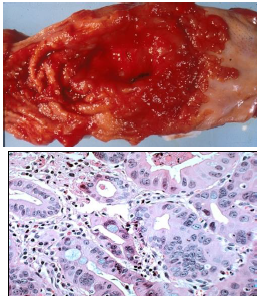

hepatocellular carcinoma malignant; increased AFP

Pathology? (liver)

focal nodular hyperplasia